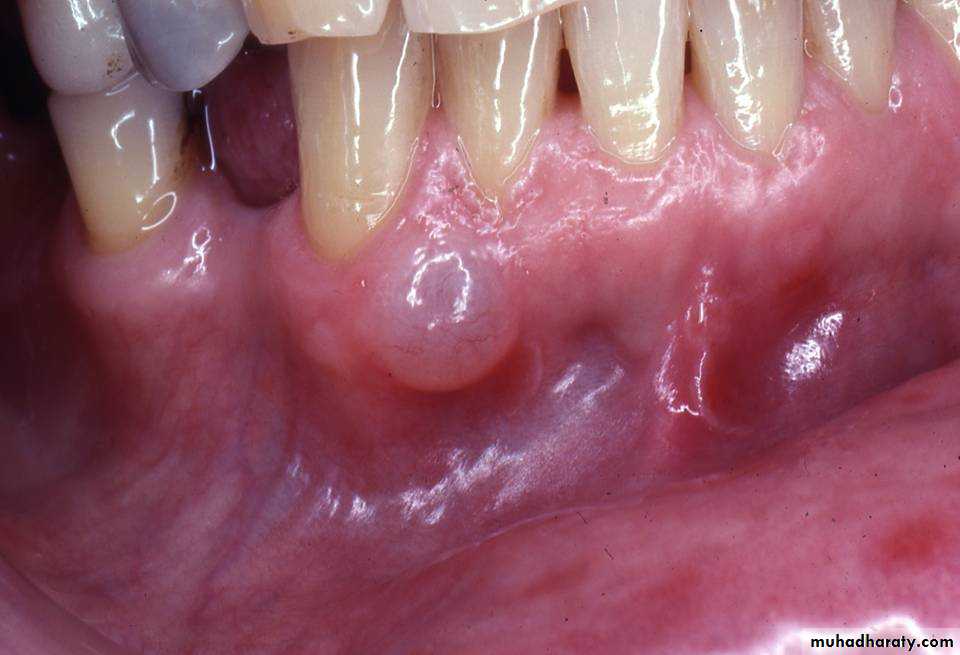

Gingival cyst

Dental lamina cyst of the newborn( Bohn's nodule).Up to 80% of newborn infants have small nodules or cyst in the gingiva due to proliferation of epithelial rest of serres.

Resolve spontaneously.

cyst ( Epstein pearl ) may arise from the non odontogenic epithelium along the midpalatal raphe, may enlarge sufficiently to appear as creamy- colourd swelling a few millimeters in diameter, but also resolve spontaneously in a matter of months.